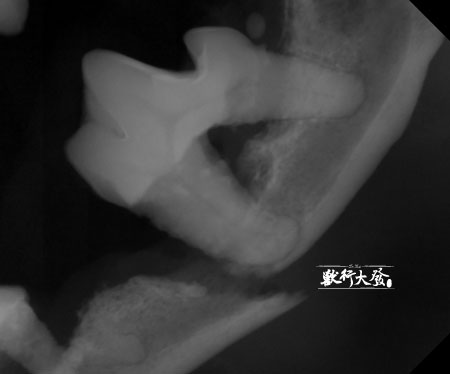

牙根X光片將骨折的斷面清楚的顯示出來

最不希望發生的出現了:左邊的下巴骨折!

這是牙周病最慘烈的併發症之一